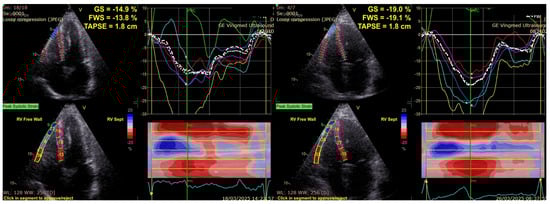

To further emphasize the limitations of conventional right ventricular function parameters, Figure 2 illustrates two representative cases, one from the diabetic group and one from the control group, which had identical TAPSE values. Despite similar conventional RV measurements, the diabetic patient showed markedly lower RV GLS and RVFWS values compared with the control, indicating impaired deformation that was not apparent on the TAPSE assessment.

Figure 2. Different values of RVGLS and RVFWS for two patients with the same TAPSE value: diabetic (left), control group (right). RVGLS, Right Ventricular Global Longitudinal Strain; RVFWS, Right Ventricular Free Wall Strain; TAPSE, Tricuspid Annular Plane Systolic Excursion.